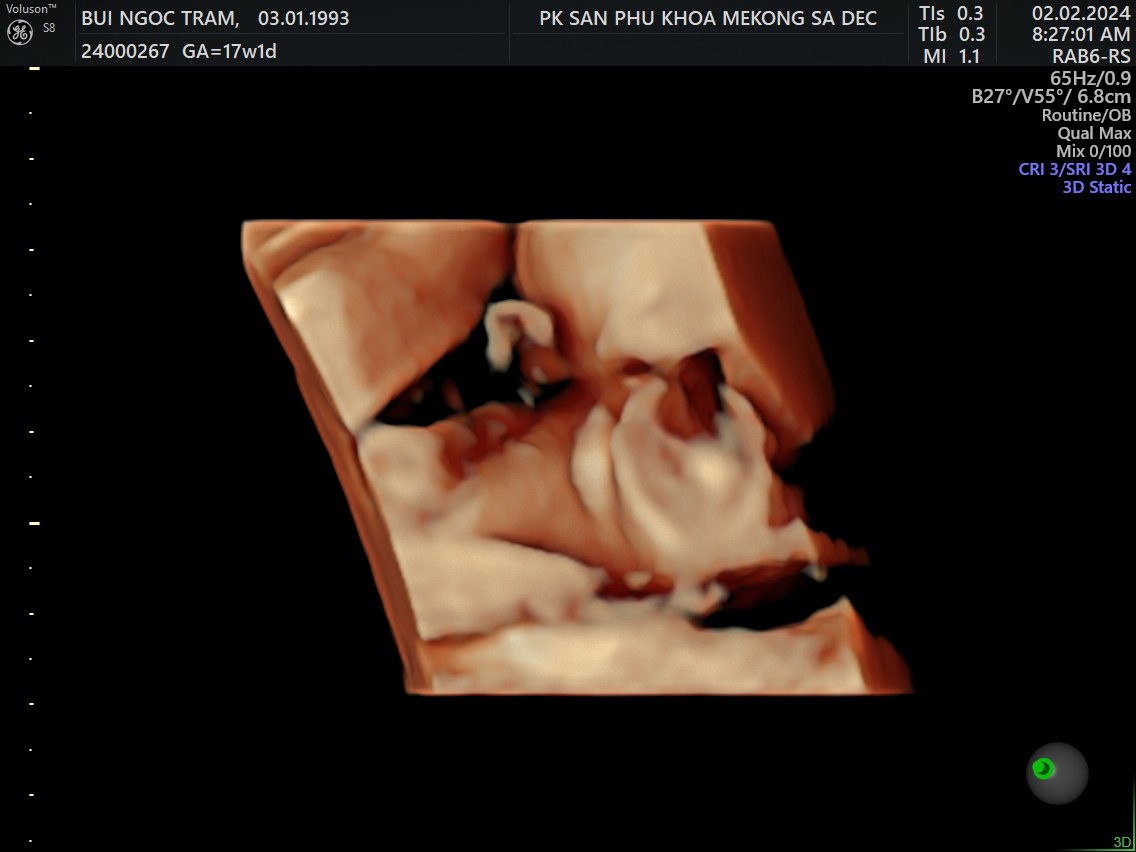

5. Siêu âm 5D

Tuần 17

2 Feb 2024

Về Sadec, được đi siêu âm 5D

Là con trai, hơi ú và hành mẹ bị viêm bạch huyết, hên là phát hiện sớm và được bác sĩ cho thuốc!